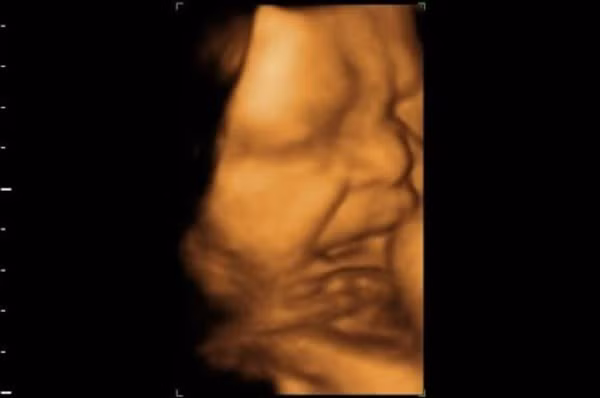

Công nghệ siêu âm đã cho phép các nhà khoa học quan sát bên trong tử cung và các bào thai đang phát triển. Năm 2005, video siêu âm được công bố trên tạp chí Archives of Disease in Childhood - Fetal and Neonatal Edition cho thấy, một thai nhi 33 tuần có biểu hiện khuôn mặt như đang khóc.

Nhóm của nhà tâm lý học Reissland đã phân tích sự phát triển của các biểu hiện trên khuôn mặt trẻ khi ở trong tử cung. Các nhà khoa học đã xem chuyển động của thai nhi trong tam cá nguyệt thứ hai và thứ ba, thông qua hình ảnh siêu âm 4D.

Năm 2011, chuyên gia Reissland và đồng nghiệp đã xác định những biểu hiện trên khuôn mặt thai nhi, bao gồm “khuôn mặt khi khóc” và “tiếng cười”. Báo cáo được đăng trên tạp chí PLOS One. Những cử chỉ đó được cho là tiền thân của các biểu hiện trên khuôn mặt khi trẻ chào đời.